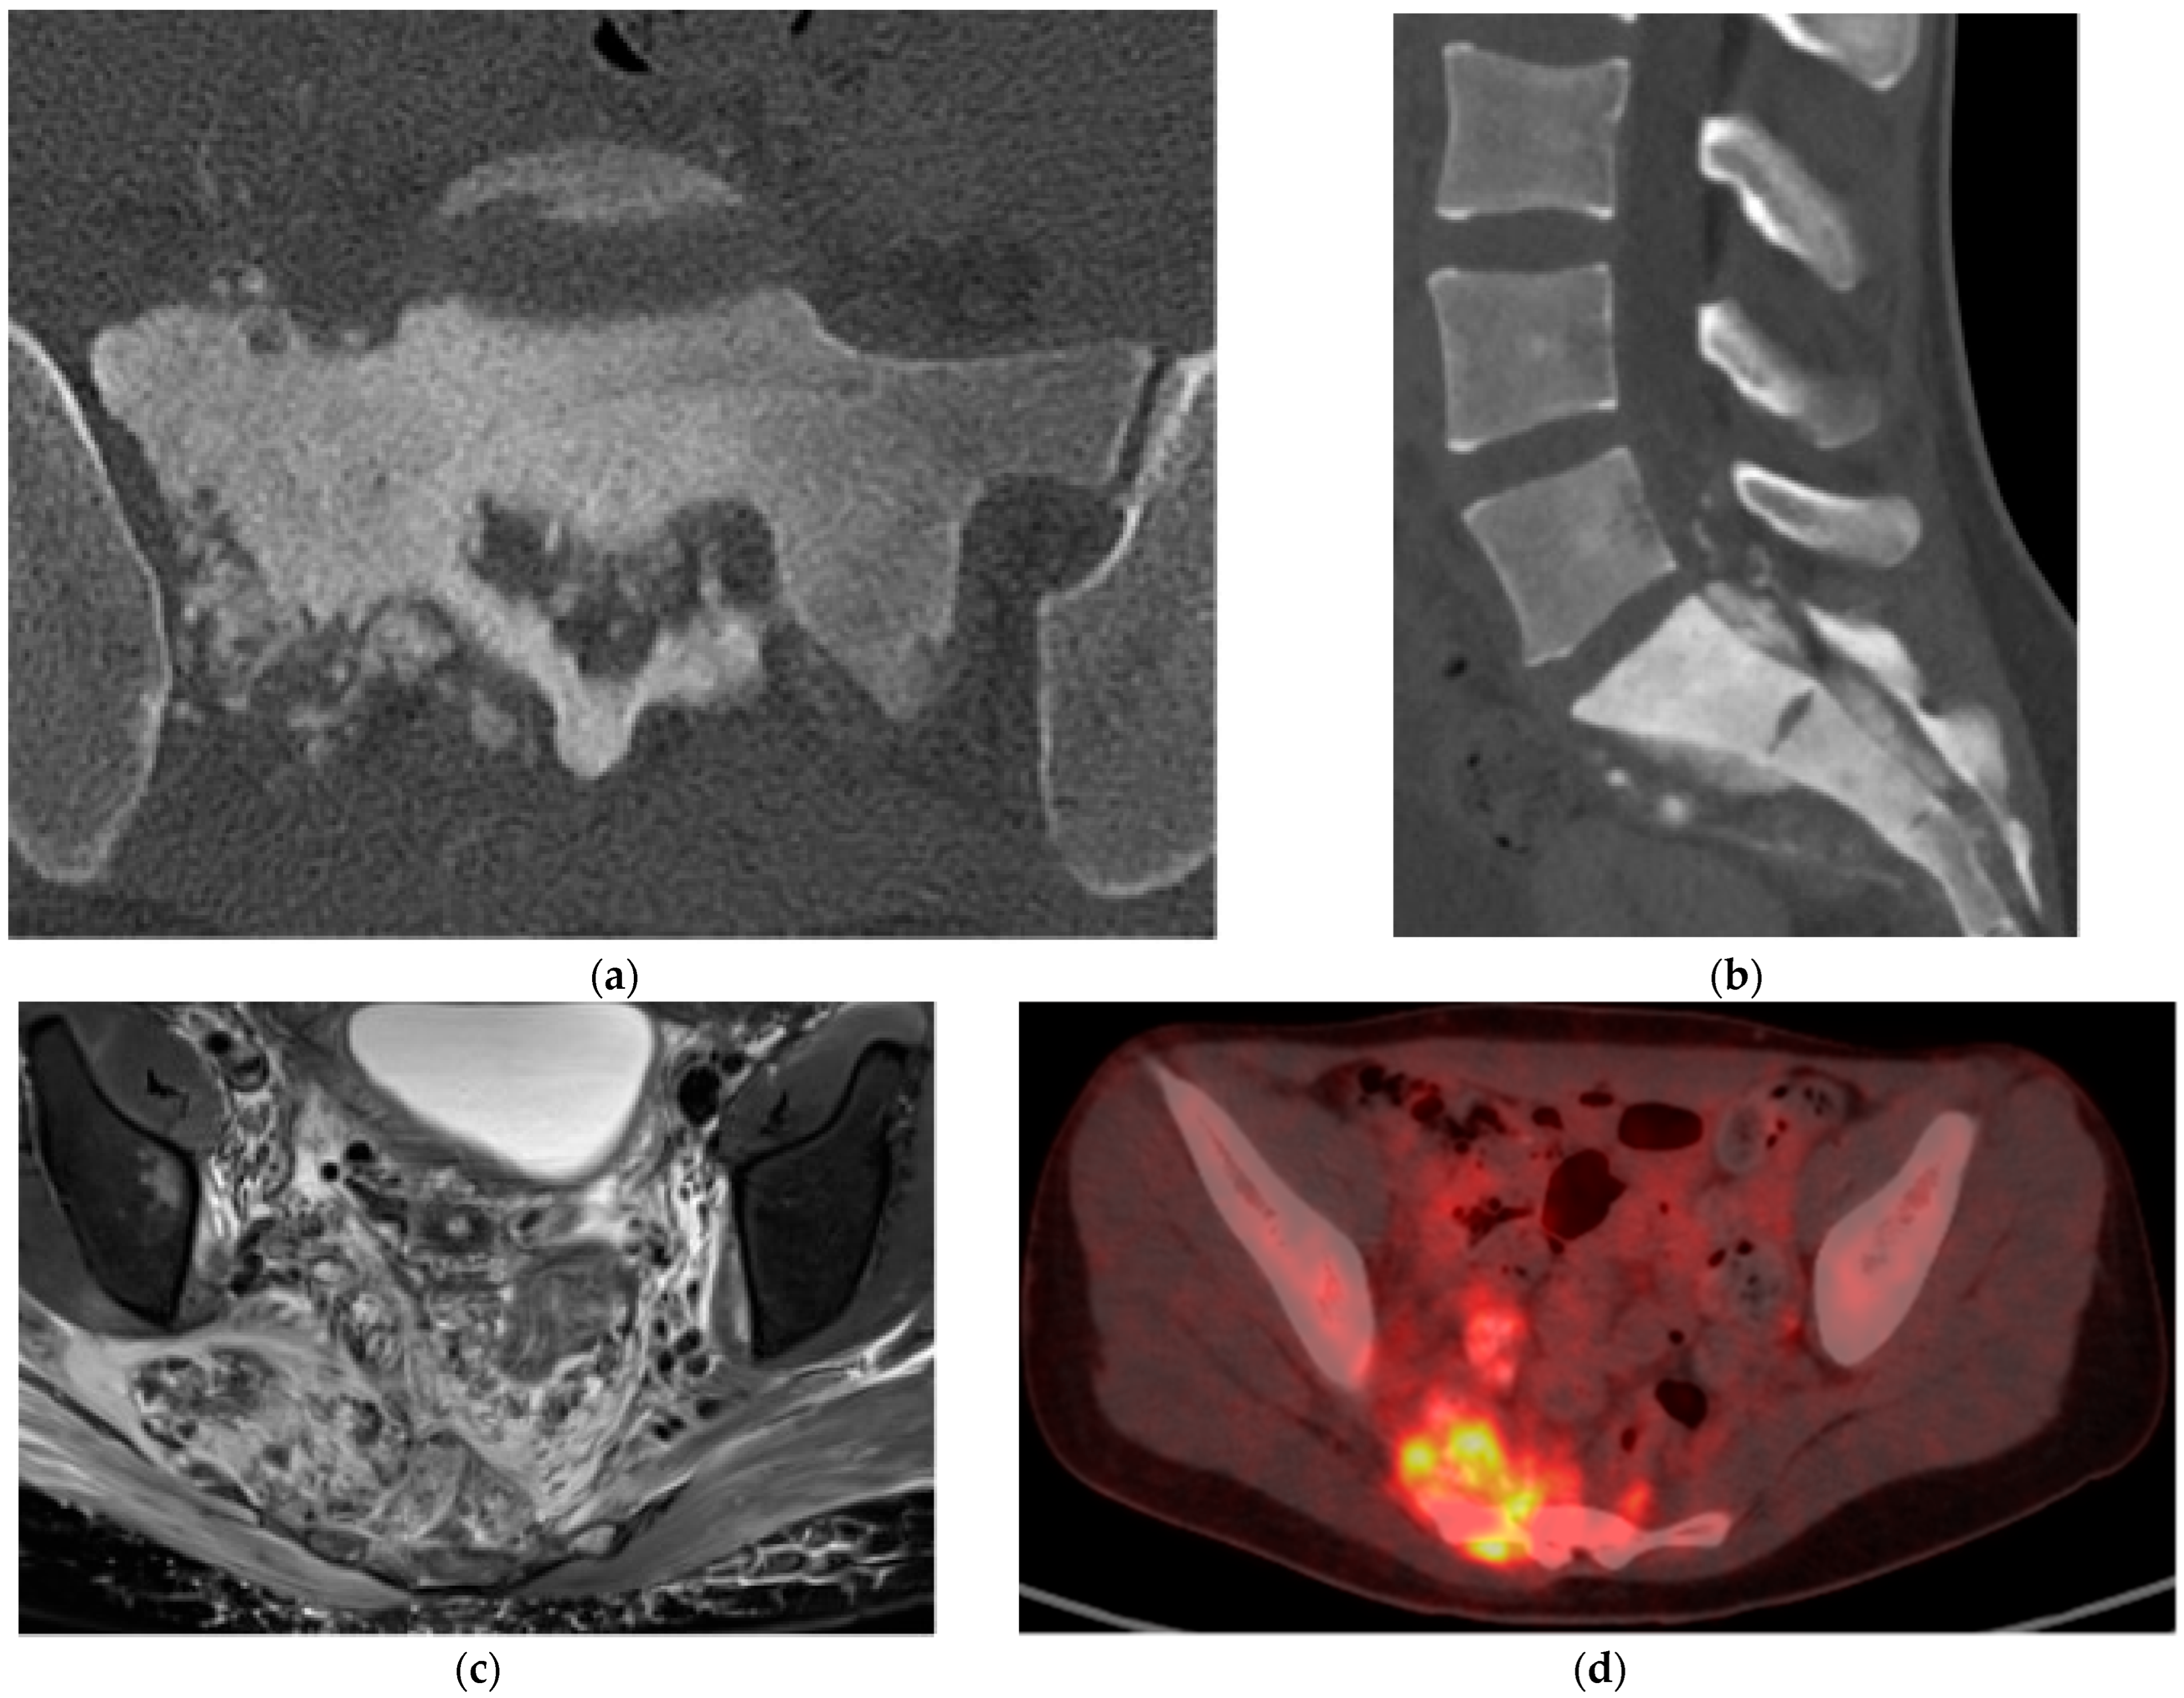

Paget’s Disease